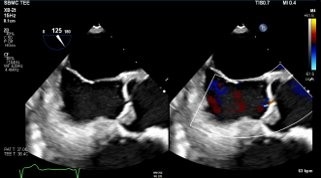

A 55-year-old male with well-controlled HIV presented with acute febrile illness, executive dysfunction, and visuo-cerebellar deficits. Initial concerns included meningoencephalitis, CNS lymphoma, and progressive multifocal leukoencephalopathy. Extensive infectious workup was unrevealing. Brain MRI revealed numerous bilateral hyperintense lesions. CT chest/abdomen identified bilateral axillary adenopathy, right pulmonary embolus, and splenic infarcts. Arterial Doppler showed a right tibial artery occlusion. Transthoracic echocardiography demonstrated aortic valve vegetations. Despite multiple embolic events, all blood cultures remained sterile, raising concern for blood culture–negative endocarditis, malignancy-associated endocarditis, and autoimmune etiologies. This prompted further serological testing for C. burnetti, B. henselae, Brucella and tumor markers, all of which were unremarkable.

Autoimmune evaluation revealed ANA >1:1280, anti-dsDNA positivity, and low complement levels, meeting the 2019 American College of Rheumatology criteria for SLE (12 points). Transesophageal echocardiography confirmed multiple echogenic densities on the aortic valve, consistent with a diagnosis of LSE in the setting of newly diagnosed SLE. LVEF was moderately reduced (35–40%) with global hypokinesis. The patient was started on therapeutic anticoagulation and guideline-directed therapy for heart failure, with rheumatology consulted for long-term treatment.